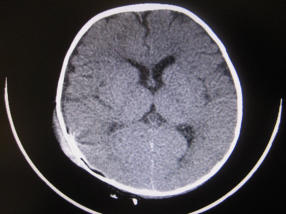

Estudio tomográfico postquirúrgico